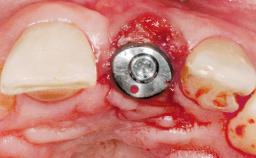

A 42-year-old female patient was referred to our clinic at the School of Dentistry of the University of São Paulo in November 2004, presenting a deficient restoration in the upper left central incisor. The clinical examination revealed no gingival retraction or any signs of gingival inflammation and, therefore, previous periodontal treatment was not considered. The patient presented a high lip line at full smile and a thin tissue biotype. This combination characterized a high-risk situation from an anatomic point of view, which required careful preoperative planning and cautious surgical execution.

Type of Implants One-Piece

Attachment One-Piece

Placement Protocol Immediate implant placement

Loading Protocol Immediate

Retention Screw-retained Screw-retained